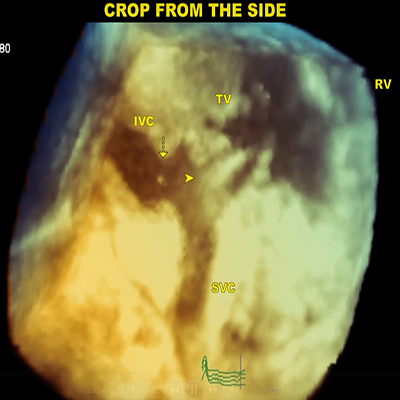

IVC filter

509 KB